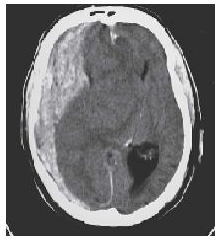

Paciente de 70 anos, diabético, hipertenso e portador de fibrilação atrial, apresentou síncope com queda no banheiro em casa há 2 horas e deu entrada no pronto-socorro queixando-se de dor na cabeça. Estava confuso, com Glasgow 12, PA 100/70 mmHg, FC 90 bpm, SPO2 96% e glicemia capilar 183 mg/dl. Evoluiu nas horas seguintes com rebaixamento do nível de consciência e necessidade de entubação e suporte hemodinâmico. Após estabilização, realizou TC de crânio sem contraste, com a seguinte imagem:

O diagnóstico para o caso acima é: